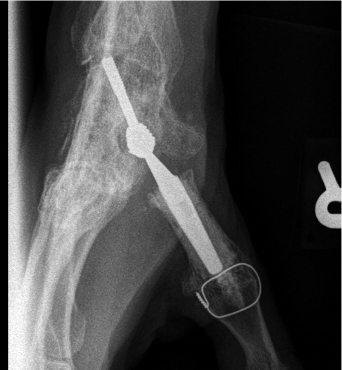

Figure 12 shows a patient aged about 60 who since 2008 has done a particularly manual job (construction industry) involving heavy loads, repetitive gestures, hammering etc. His doctor suggested CMC arthrodesis due to the mechanical restrictions which meant an implant was almost certainly infeasible. This was a wise decision, because the patient was able to continue working despite having limited movement in the thumb, with no significant pain.

For the past few months, he has experienced progressive STT pain, which was worse when carrying loads and doing the thumb-finger pinch grip. The discussion with the patient soon turned to surgical options due to the lack of any clear improvement with orthotics. The solutions discussed were:

- Trapezium excision and interposition (requiring reversal of the CMC joint fusion)

- STT arthrodesis, quickly ruled out for functional reasons

- Distal scaphoid excision and tendon interposition

- Distal scaphoid resurfacing.

It did not take long to decide on resurfacing using the INCA implant (Figure 13), saving tendon imposition for the event of failure.